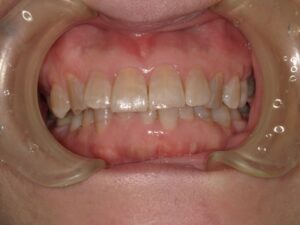

笑った時に、歯ぐきが見えるのをガミースマイルと言います。

ガミースマイル(Gummy Smile)とは、笑ったときに上唇が上がって、歯ぐき(歯肉)がよく見えてしまう状態を指します。審美的な問題として気にされる方が、ことのほか多いです。原因も様々で、それぞれ治療法が異なります。歯科的な治療法と歯科以外の治療法を説明していきます。ただし原因にかかわらず、治療による改善は難しいことが多いです。